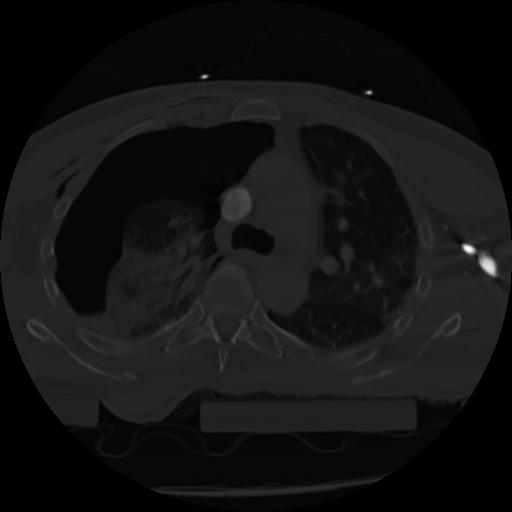

21 ANGIO,CE,Axial,3.0,ANGIO,,